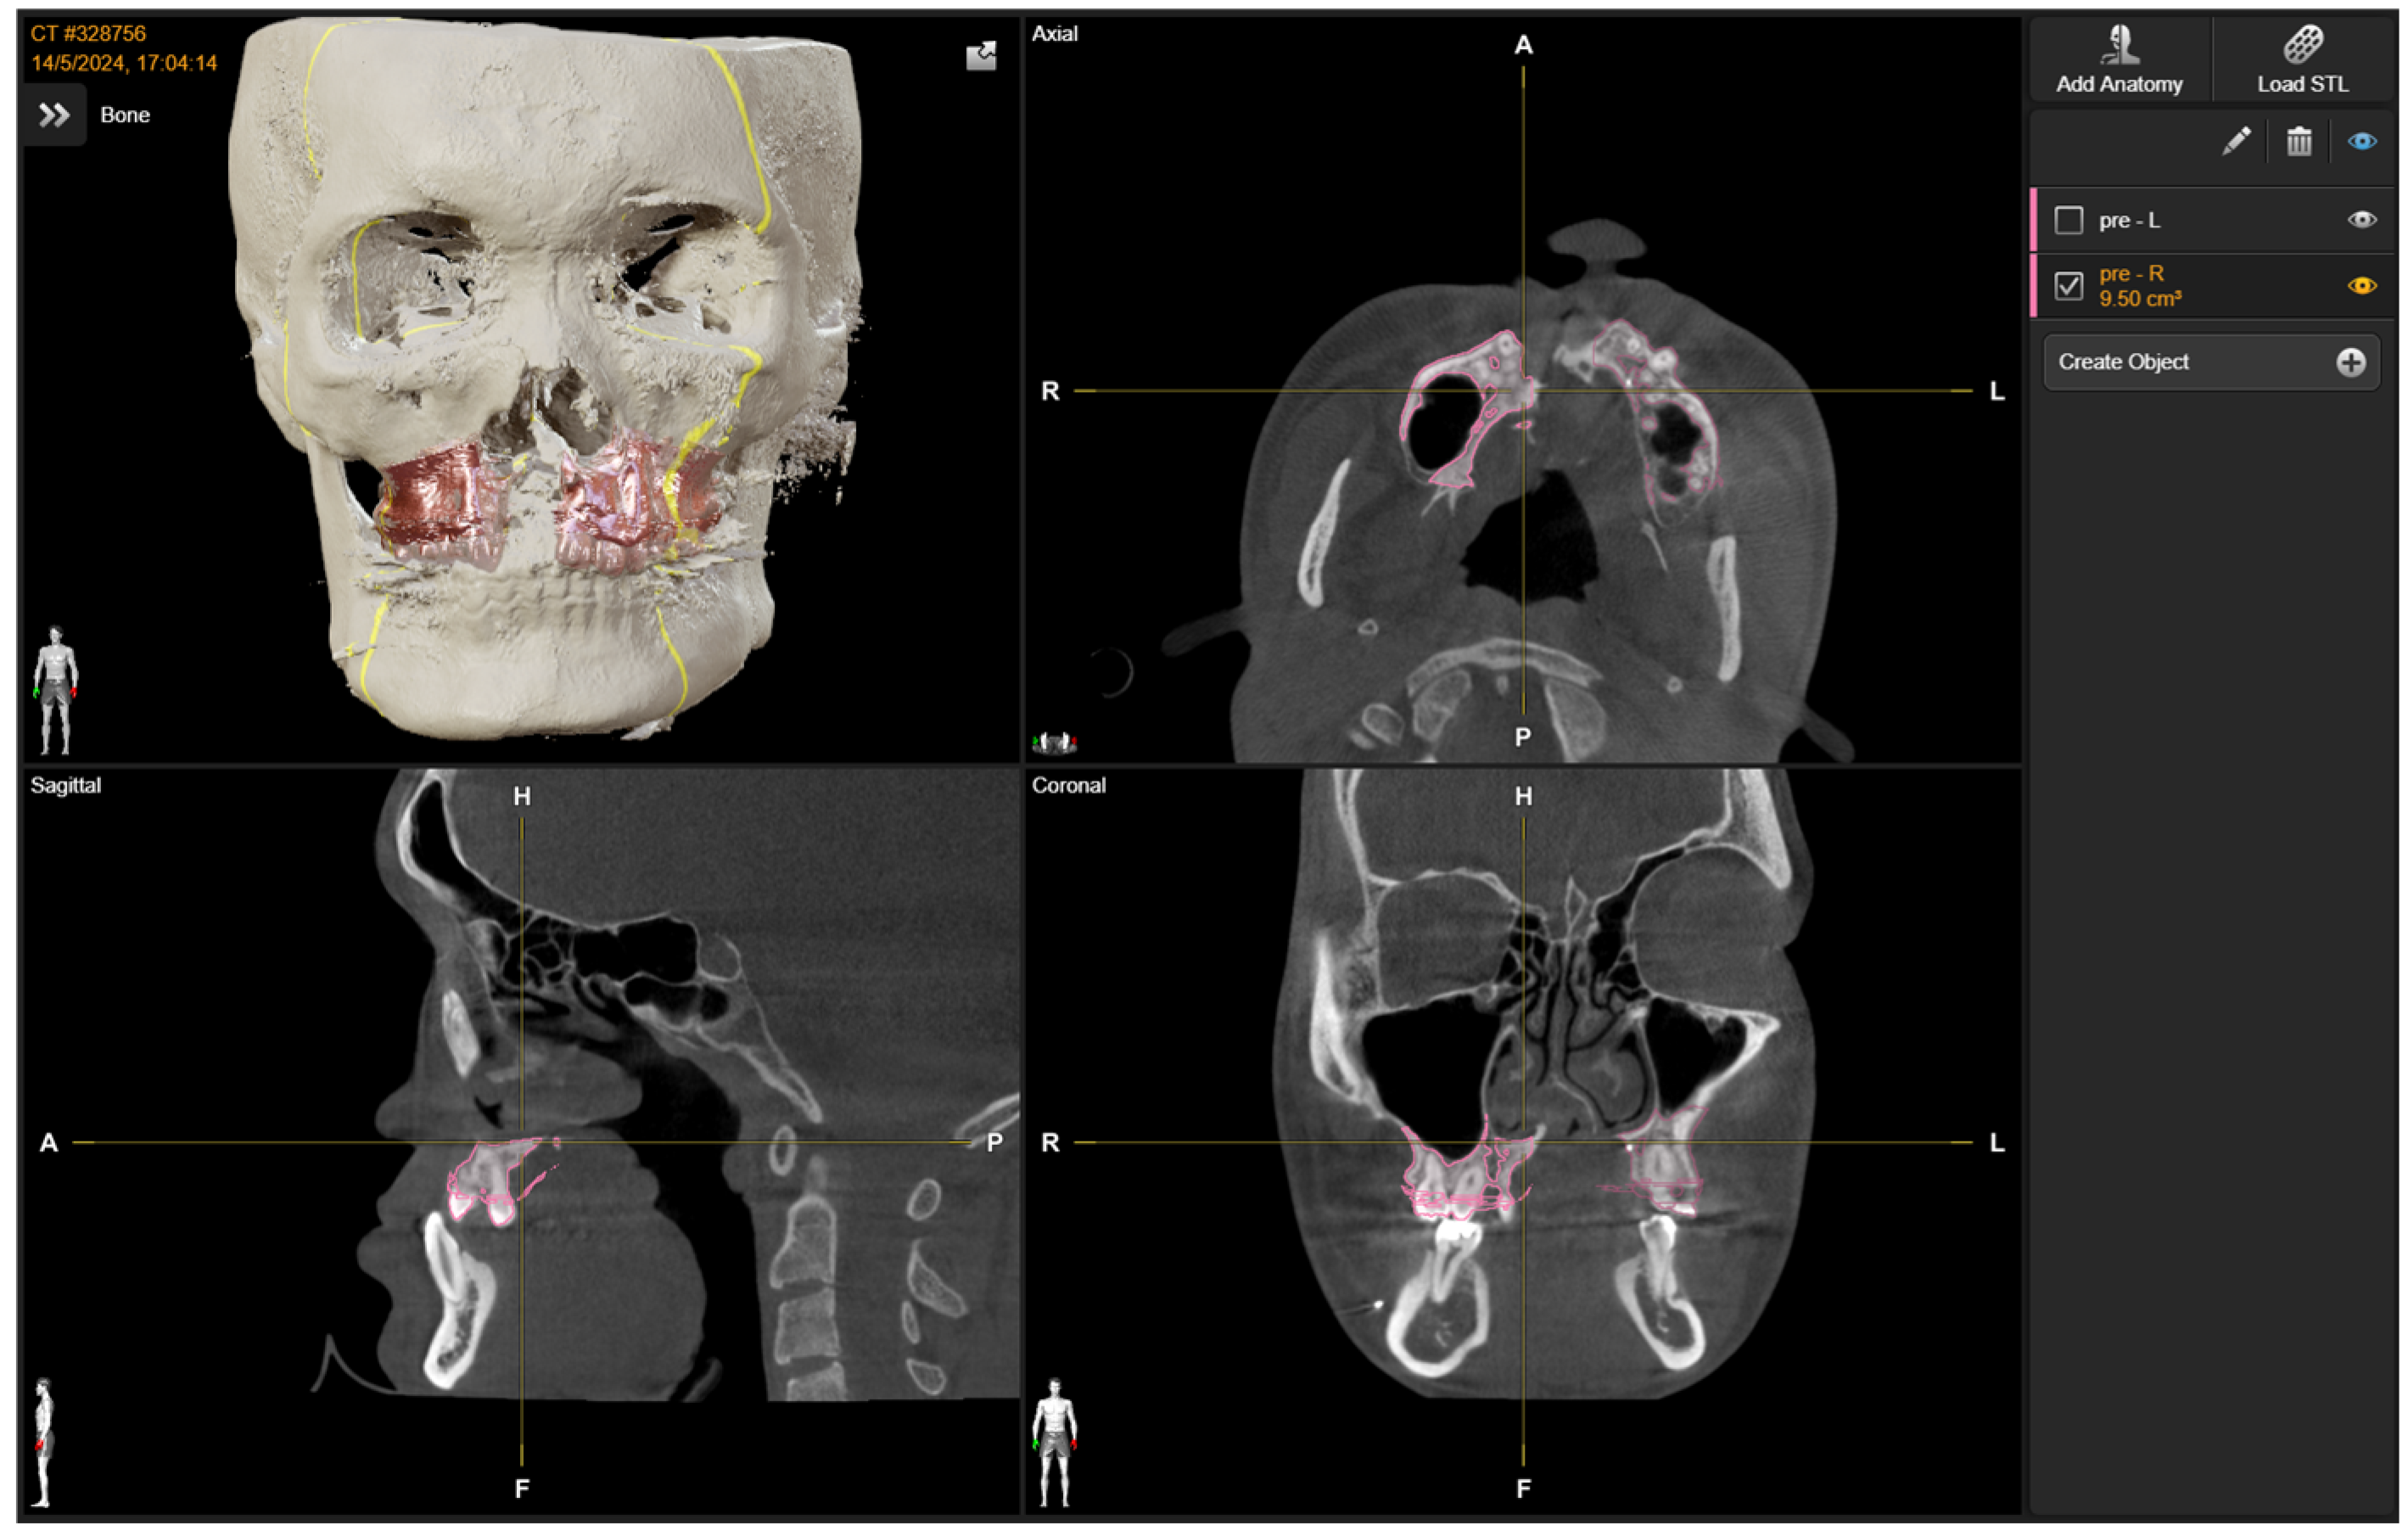

2. Materials and Methods

2.1. Preoperative Planning

2.2. Intra-Operative Navigation